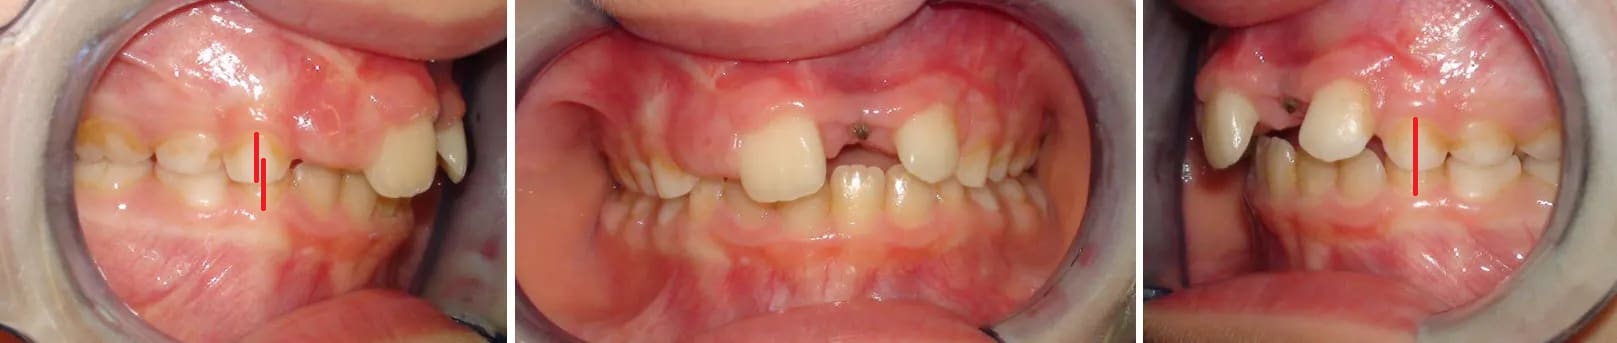

Et voici le cas de cette jeune fille deux ans plus tard, elle a alors 9 ans. On va encore attendre.

Cette fois elle a 10, on va démarrer quelque chose, mais quoi ?

On ouvre pour remplacer à terme la 21 ou est-ce qu'on ferme l'espace ?

Votre avis ?

Après connaissance des photos EB/IB/Radios de Maître Dancha, je note la Classe II Dentaire FULL Supra, avec déviation +++ des milieux ... Un indice ?

A ajouter axes 11/23, reste 65/75/85...